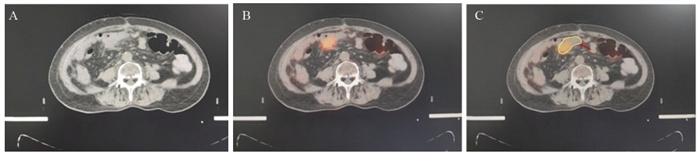

方法 采用18F-FDG PET-CT对38例治疗后复发的腹盆腔肿瘤患者进行模拟定位, 分别根据CT影像及18F-FDG PET-CT拟定全身治疗方案及放疗靶区勾画, 对比二者差异。

结果 在38例患者中, 21.1%(8/38)发现了盆腹腔外远处转移, 改变了治疗方案。34例(89.5%)放射治疗靶区发生了改变。GTVPET-CT的均值为118.14 cm3, GTVCT的均值为148.53 cm3(P=0.044)。

结论 18F-FDG PET-CT模拟定位对于复发盆腹腔肿瘤患者, 完善了肿瘤再分期, 改变了部分患者治疗方案, 更加精确放射治疗靶区。